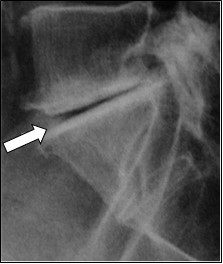

Na rentgenogramie przedstawione jest złamanie Saltera-Harrisa typu

Ilustracja do pytania 19

A. II odcinka bliższego kości piszczelowej.

B. V czwartej kości śródręcza.

C. I ześlizgnięcie bliższej nasady kości udowej lewej.

D. III nasady dalszej kości piszczelowej.